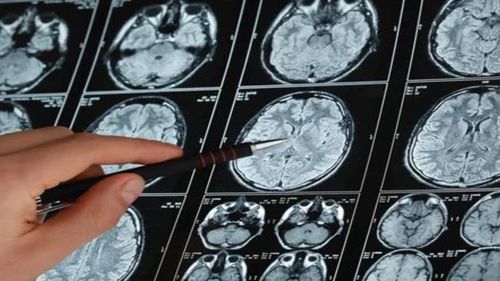

Beyinde pıhtı oluşumu, felç gibi ciddi sağlık sorunlarına neden olabilir. Bu durum, acil müdahale gerektirir ve hayat kurtarıcı olabilir. Beyne pıhtı atması nedir, belirtileri nelerdir ve önlenir? İşte detaylar... BEYNE PIHTI ATMASI NEDİR, NASIL ANLAŞILIR? Beyne pıhtı atması, beyin damarlarının…